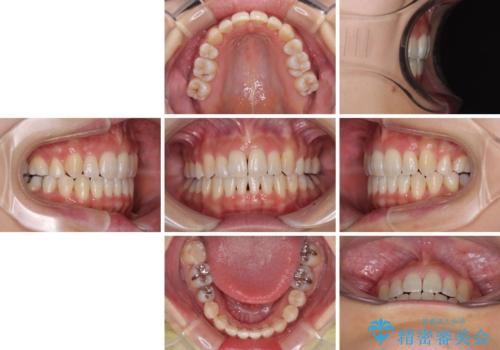

- 目立つ八重歯を気にして来院された患者様です。

下顎歯列の叢生は軽度であることと、口元の突出感が全くなかったことから、八重歯解消のために上顎左右第一小臼歯を抜歯し、ワイヤー装置にて矯正治療を行うこととしました。

八重歯をスムーズに解消するために、補助装置を用いることで速やかに歯列を整えることができました。